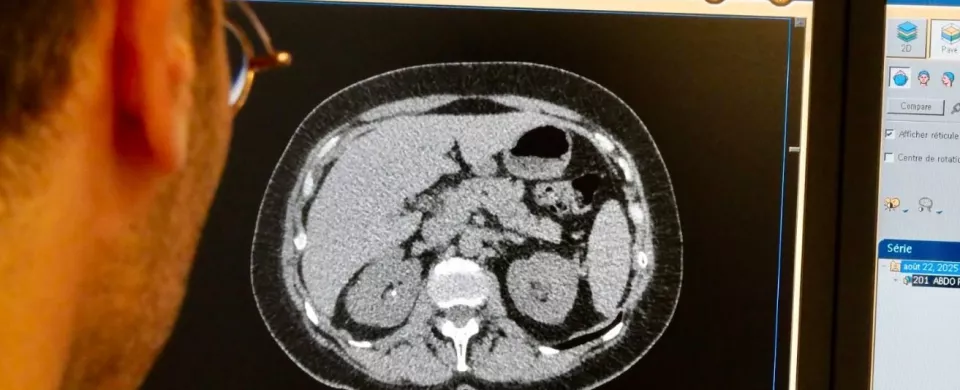

Scanner de repérage

C’est une étape importante de la préparation du traitement, durant laquelle le radiothérapeute et le manipulateur repèrent la région à traiter à l’aide du scanner et choisissent la position adaptée. Nous utilisons souvent des moyens pour vous aider à ne pas bouger (cales, coussins, masques…), dont nous nous servirons pendant votre traitement. Des repères sont tracés sur votre peau (encre temporaire ou tatouages permanents), qui sont indispensables à la réalisation de votre traitement et doivent être gardés pendant la durée de celui-ci. Cette séance, de durée variable, n’est pas douloureuse. Elle nécessite votre coopération. Nous vous recommandons de vous munir de vêtements pratiques, confortables et ne craignant pas les tâches. Par mesure de précaution, une photographie d’identité et une photographie de positionnement seront prises avec votre accord.